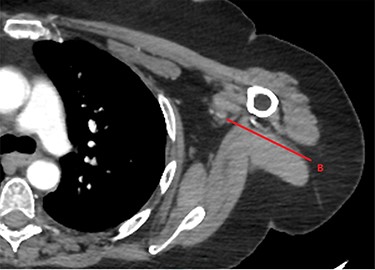

Approximately an hour later, she developed symptoms of pain and weakness to her left arm (the opposite side). Her arm was clinically assessed as cool to touch with a delayed capillary refill with pulses absent. A computed tomography angiogram (CTA) of her left arm was arranged which revealed an abrupt stop in the left axillary artery (Figs 2 and 3) with reconstitution of the vessels in the antecubital fossa. She was taken to theatre for a brachial embolectomy to re-establish blood flow to her acutely ischaemic arm.

CTA of left upper limb in the coronal plane. X—axillary artery with contrast showing flow as evident in transverse imaging (see Fig. 3), patent in the transverse plane marked A. Flow ceases approximately at the level of the plane marked B. Y—axillary artery occluded as shown with contrast absent.